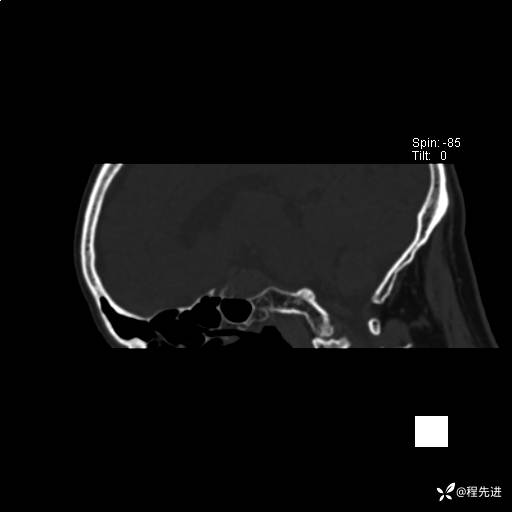

患者性别:男

患者年龄:74岁

简要病史:出现视物重影2月余,未予重视,2月来症状逐渐加重

实验室检查:无特殊

CT平扫: